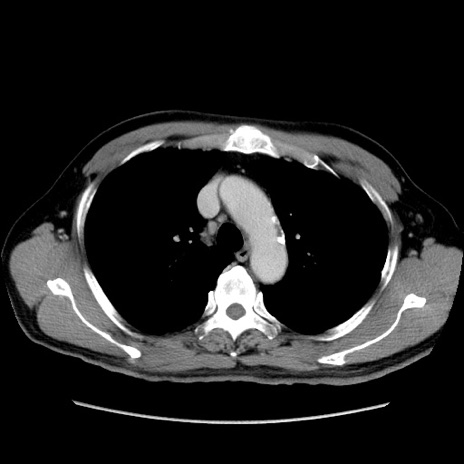

【症例】60歳代 男性

【主訴】右鼠径部膨隆

【現病歴】1年程前より右鼠径部膨隆あり。自己にて還納可能だったため放置していた。3時間前より右鼠径部の脱出を認め、還納困難となり受診。

【既往歴】高血圧

【身体所見】右鼠径部に小児頭大の膨隆あり。弾性硬であり、用手還納は困難。左鼠径部にも膨隆を認める。脱出はなし。